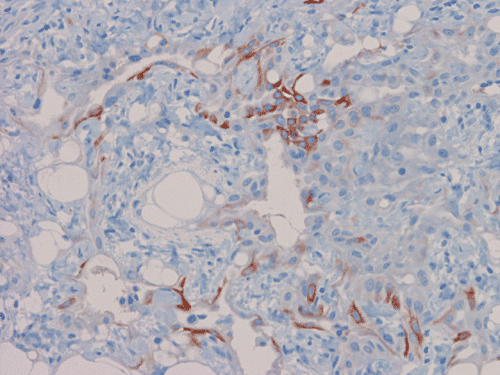

Calretinin

On scanning magnification, there is a round lesion in tissue around the fallopian tube (arrows in Panel A). The lesion does not invade into the tube nor distort or compress the tube. The cross sectional dimension is about the same diameter of the fallopian tube. On low and medium magnification, the lesion is composed of a collection of small microcysts intermingled with the smooth muscle bundles of the wall of the fallopian tube (Panel B and C). On higher magnification, the cyst or gland like spaces are lined by epithelioid to spindle cells with bland nuclei and an abundant amount of amphophilic cytoplasm (Panel D and E). The spindle cells are positive for calretinin, cytokeratin 5/6, and inhibin (Panel F, G, and H).

Immunohistochemically, adenomatoid tumor is positive of cytokeratin. This may confuses their distinction from adenocarcinoma further. Because of their mesothelial orign, they are positive for calretinin, cytokeratin 5/6, and WT-1. These tumors are negative or at most weakly positive for carcinomembryonic antigen (CEA), Ber-EP4, and B72.3. As demonstrated in this case, they can be positive for inhibin. These featues help to differentiate adenomatoid tumor from adenocarcinoma.